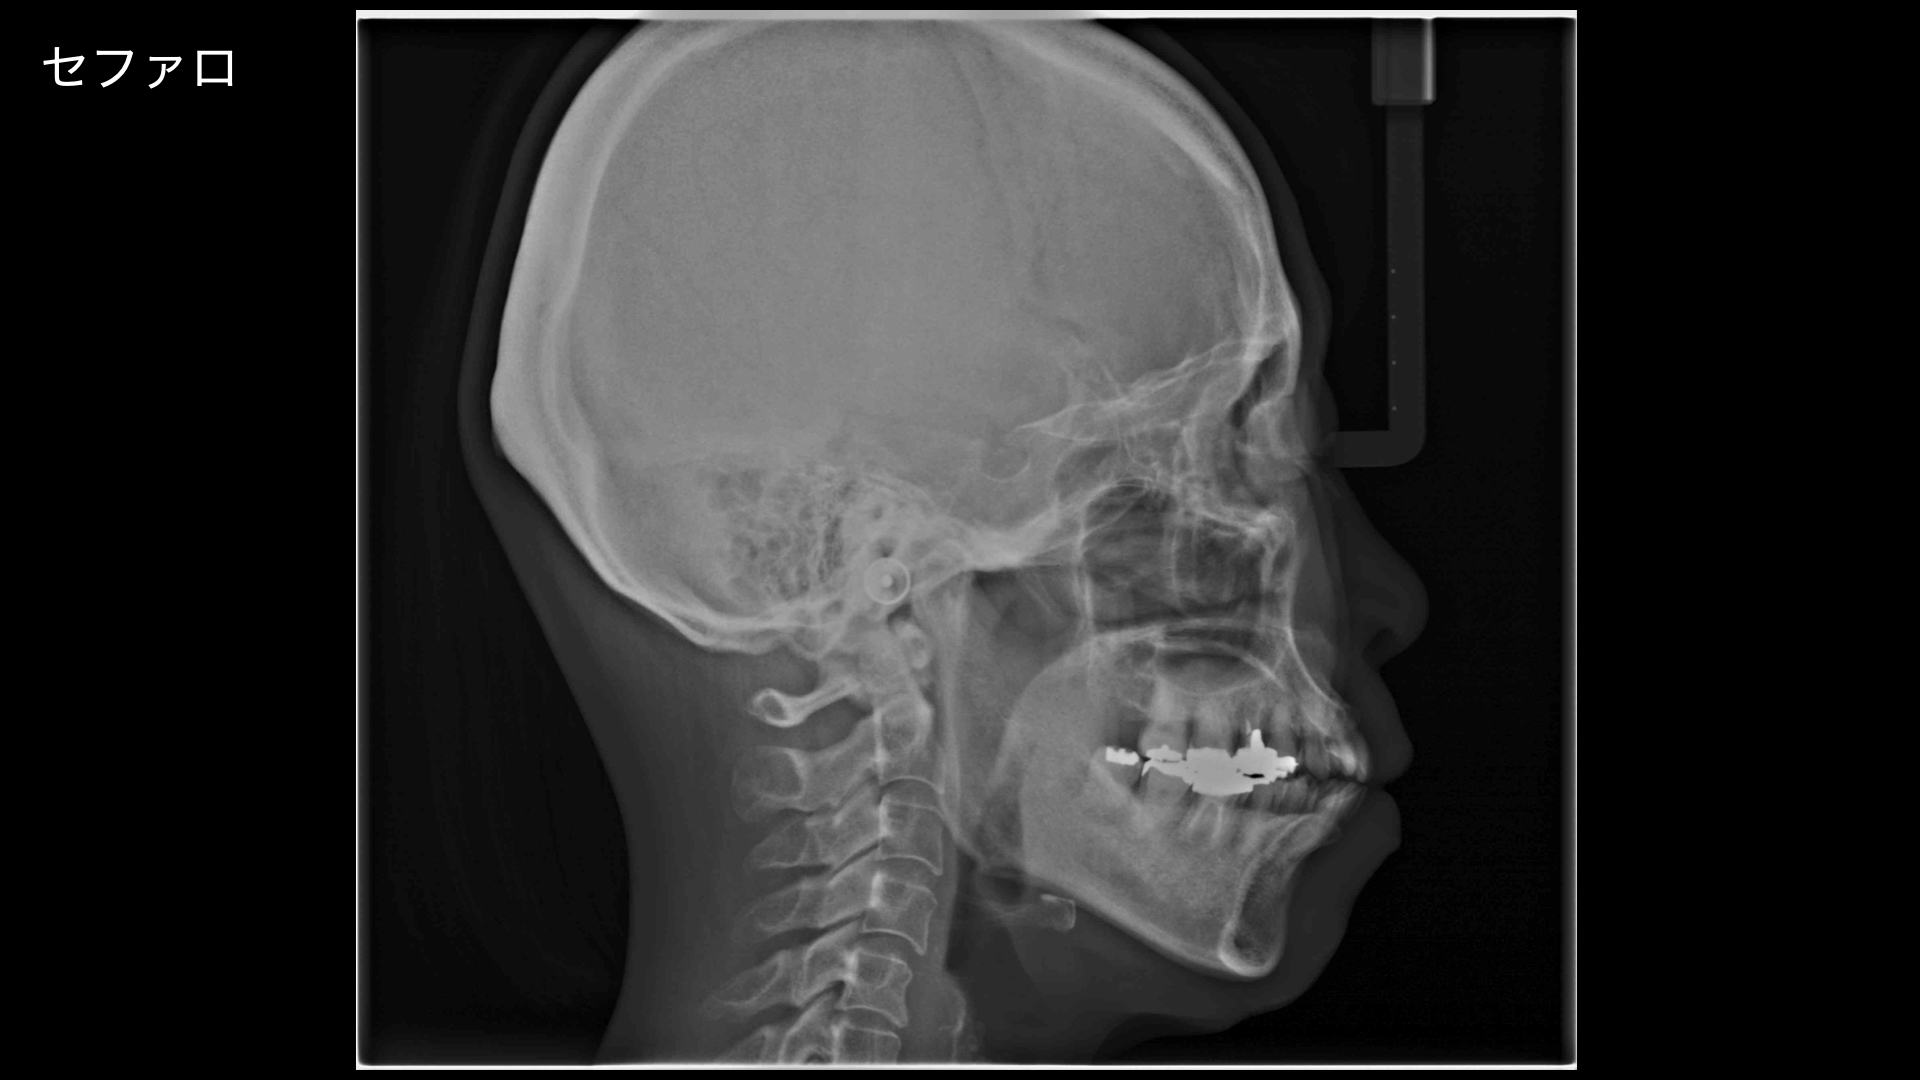

矯正の診断をおこないました。

どうしても全体的な矯正治療(平均2〜3年)を望まれなかったので、模型上で咬合調整をおこない、やや前歯が噛み合うところまで調整すると矯正治療期間が短くなります。

模型上で、そこから歯を並べて(排列)みて奥歯をさわらずに短い期間で矯正治療ができるのかをシミュレーションした結果

可能ということがわかったので、この計画にしました。